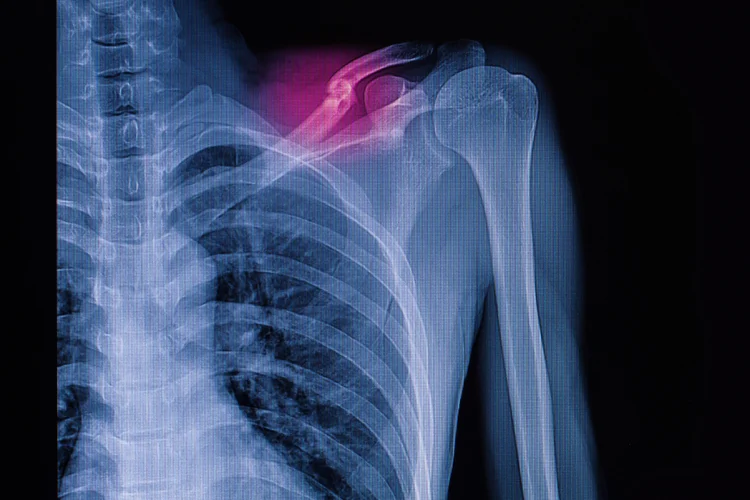

Collarbone (Clavicle) Fracture: Symptoms & Treatment

A collarbone (clavicle) fracture is a break in the clavicle, the long, slender bone

connecting the shoulder to the chest. This type of fracture is common in both

children and adults, often resulting from direct impact, falls, or sports injuries.

- X-ray – Using low-dose radiation, an X-ray captures images of the clavicle to confirm the fracture, assess bone displacement, and determine its severity.